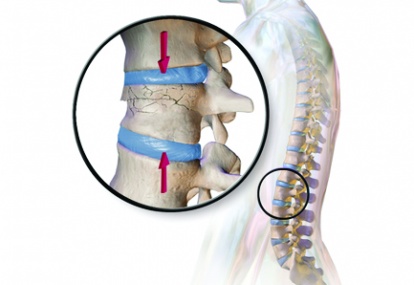

Case study 1: Vertebral compression fracture

An 80-year-old woman presented at the emergency department with sudden onset of acute severe back pain for the past few days

The pain is aggravated by gentle movement and shows some relief with rest. She has a background history of osteoporosis and chronic...